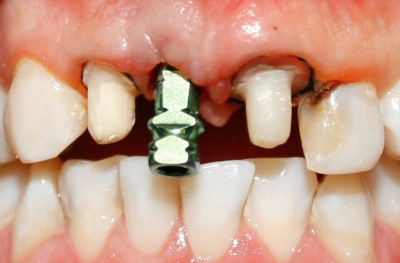

Se remueve tornillo de cicatrización

Vista clínica implante